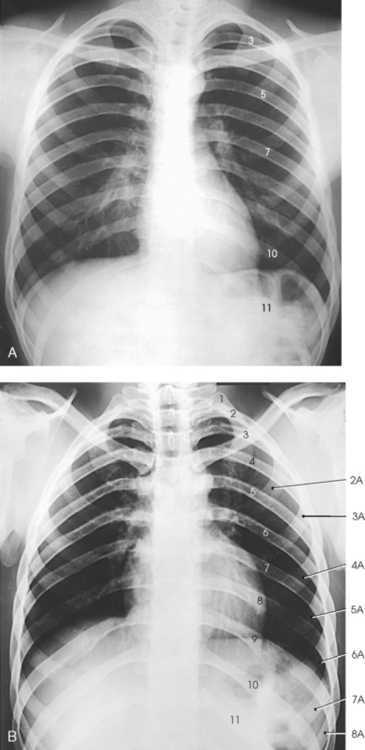

The 12 pairs of ribs are numbered consecutively from superiorly to inferiorly (Fig. 9-4; see Figs. 9-1 and 9-2). The rib number corresponds to the thoracic vertebra to which it attaches. Each rib is a long, narrow, curved bone with an anteriorly attached piece of hyaline cartilage, the costal cartilage. The costal cartilages of the first through seventh ribs attach directly to the sternum. The costal cartilages of the 8th through 10th ribs attach to the costal cartilage of the 7th rib. The ribs are situated in an oblique plane slanting anteriorly and inferiorly so that their anterior ends lie 3 to 5 inches (7.6 to 12.5 cm) below the level of their vertebral ends. The degree of obliquity gradually increases from the 1st to the 9th rib and then decreases to the 12th rib. The first seven ribs are called true ribs because they attach directly to the sternum. Ribs 8 to 12 are called false ribs because they do not attach directly to the sternum. The last two ribs (11th and 12th ribs) are often called floating ribs because they are attached only to the vertebrae. The spaces between the ribs are referred to as the intercostal spaces.

The ribs located above the diaphragm are best examined radiographically through the air-filled lungs, whereas the ribs situated below the diaphragm must be examined through the upper abdomen. Because of the difference in penetration required for the two regions, the position and respiratory excursion of the diaphragm play a large role in radiography of the ribs.

The position of the diaphragm varies with body habitus: It is at a higher level in hypersthenic patients and at a lower level in asthenic patients (Fig. 9-9). In sthenic patients of average size and shape, the right side of the diaphragm arches posteriorly from the level of about the 6th or 7th costal cartilage to the level of the 9th or 10th thoracic vertebra when the body is in the upright position. The left side of the diaphragm lies at a slightly lower level. Because of the oblique location of the ribs and the diaphragm, several pairs of ribs appear on radiographs to lie partly above and partly below the diaphragm.

Fig. 9-9 Diaphragm position and body habitus. A, A hypersthenic patient has a diaphragm positioned higher. B, An asthenic patient has a diaphragm positioned lower. C, Chest radiograph of a hypersthenic patient. D, Chest radiograph of an asthenic patient. Note position of diaphragm on these extremely different body types.